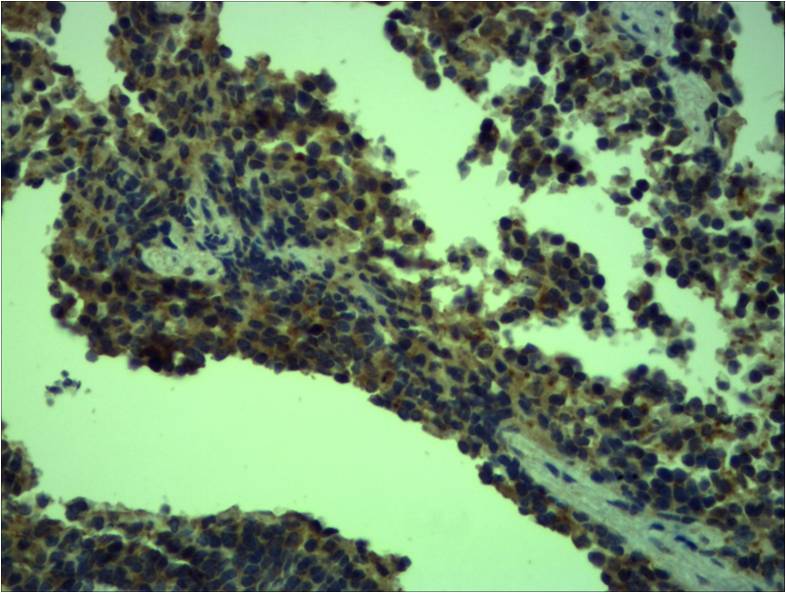

分类: 科研抗体货号: P23172别名: STEAP2; PCANAP1; STAMP1; Metalloreductase STEAP2; Prostate cancer-associated protein 1; Protein up-regulated in metastatic prostate cancer; PUMPCn; Six-transmembrane epithelial antigen of prostate 2; SixTransMembrane protein of prostate 1应用: IHC,IF反应种属: Human,Mouse